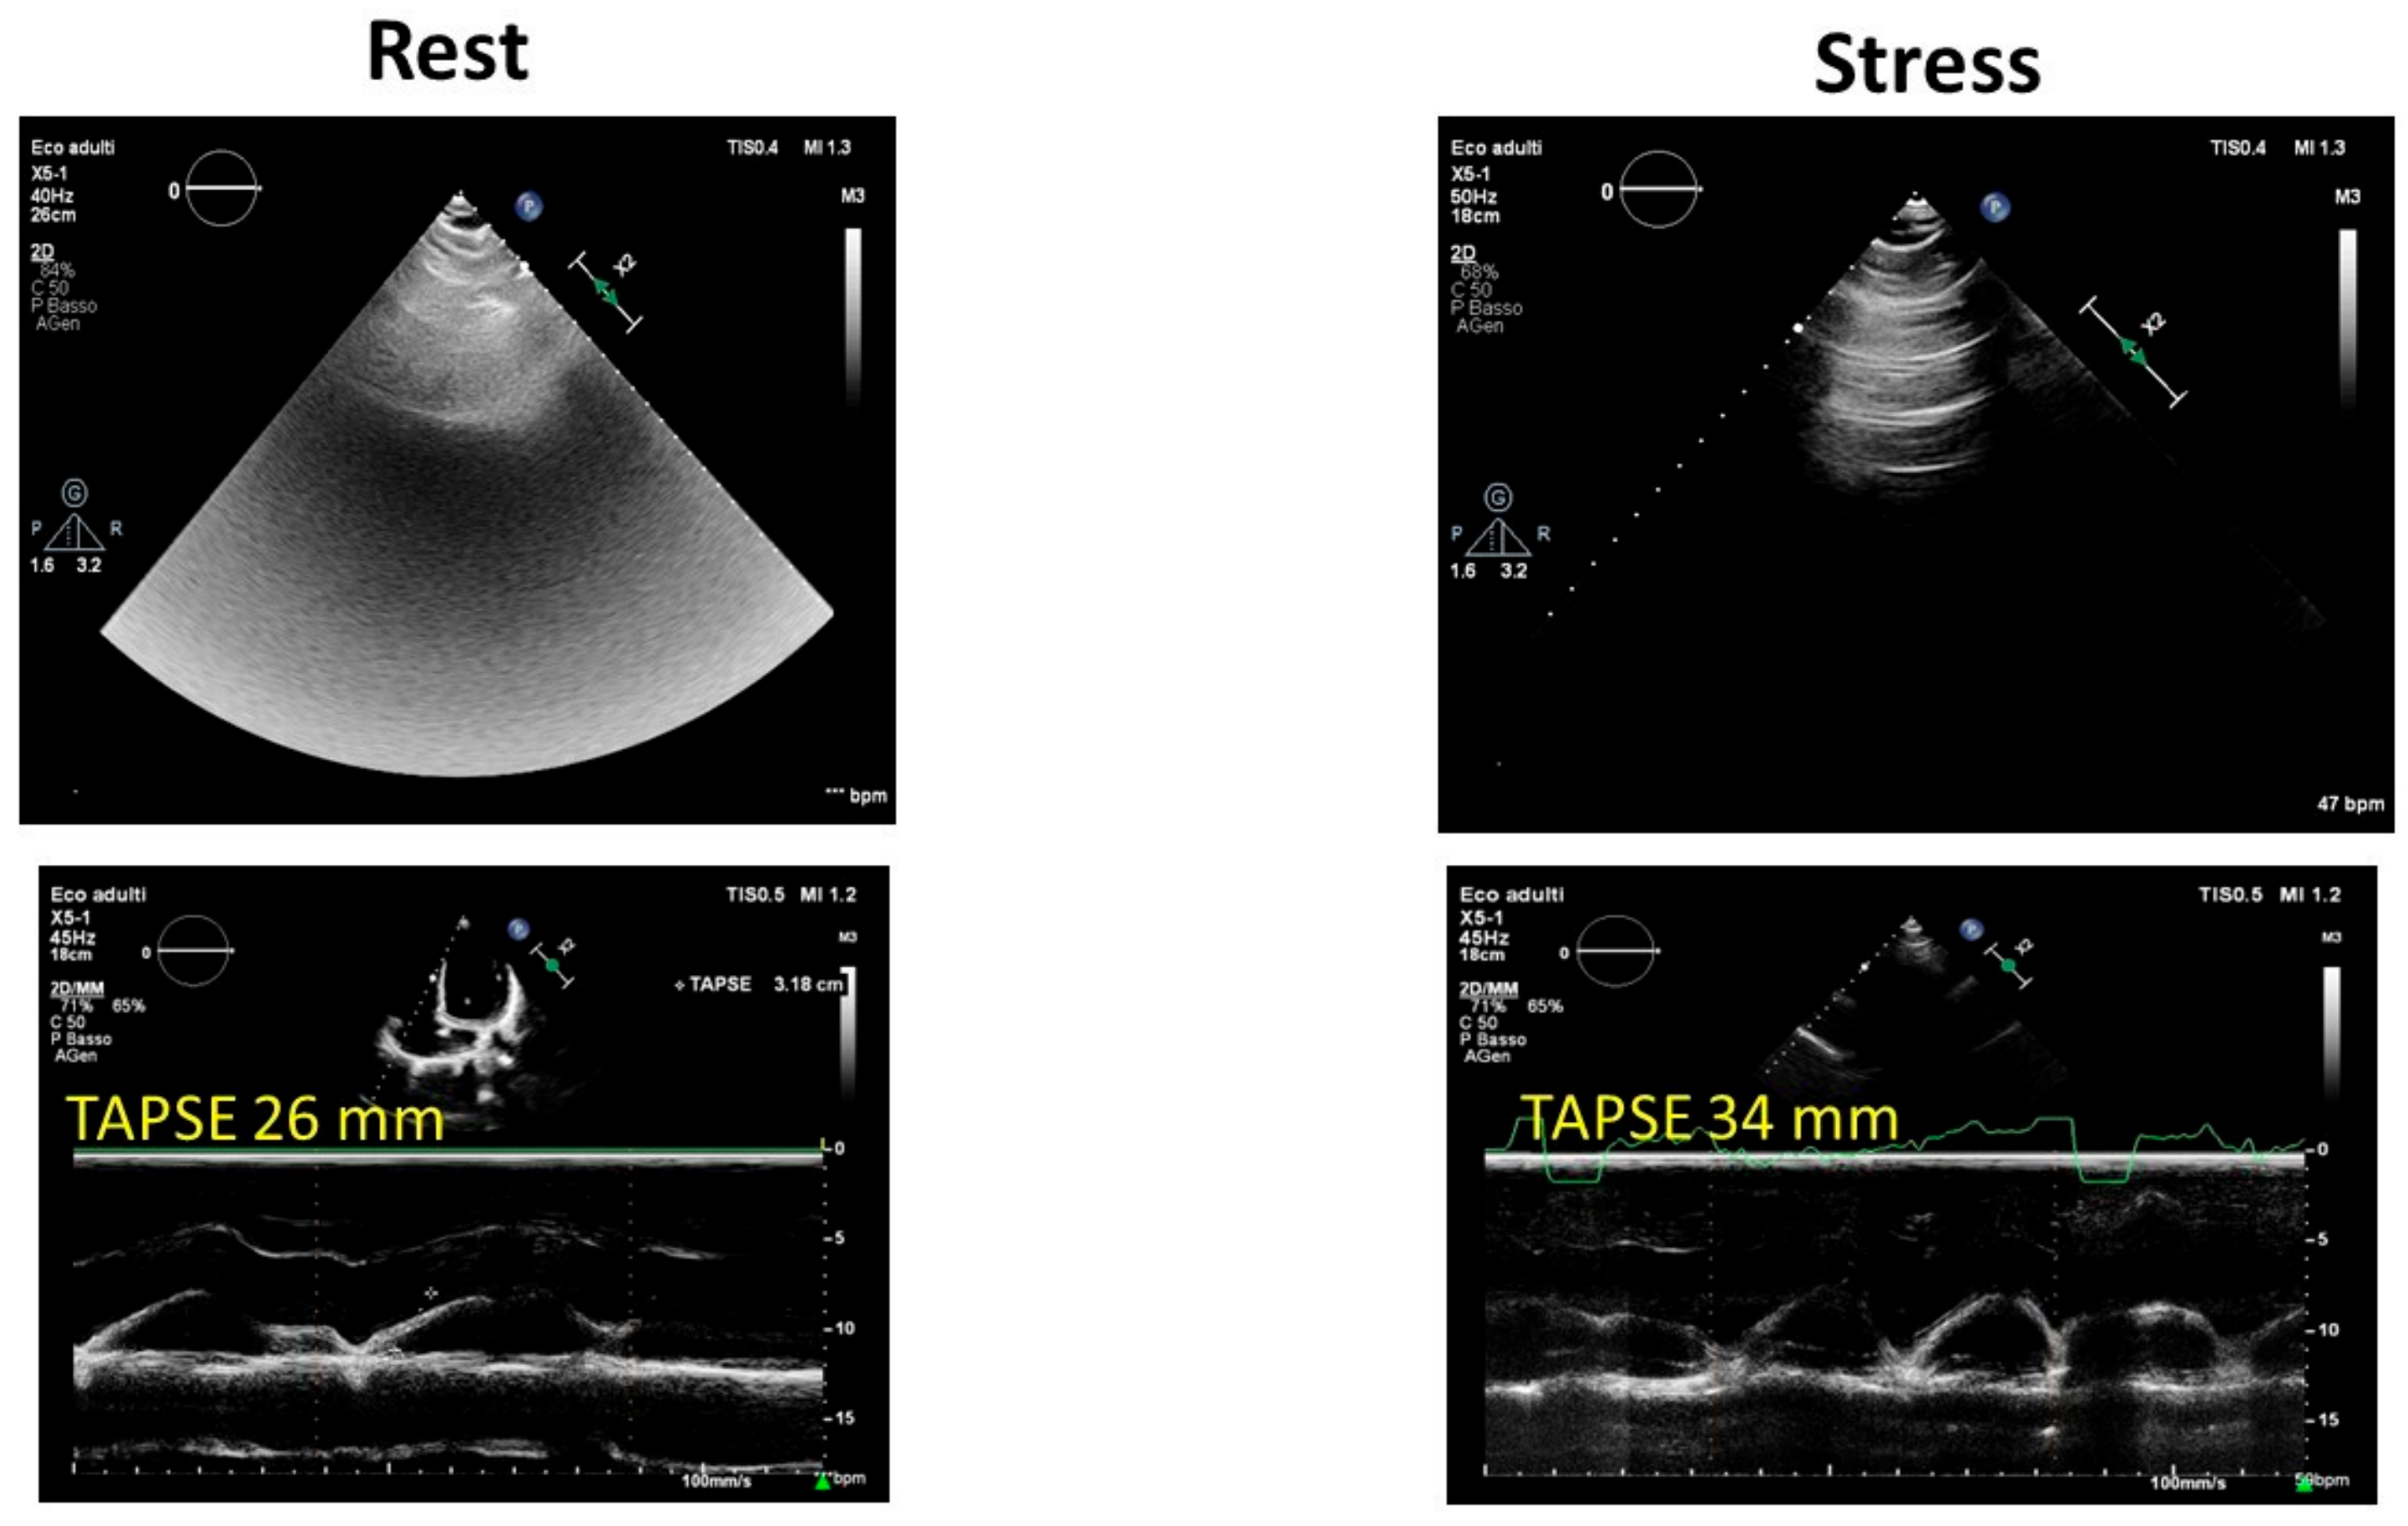

2.4. Valvular Heart Disease

| Heart valve diseases | Absent | Dynamic/functional new onset/worsening valve diseases |